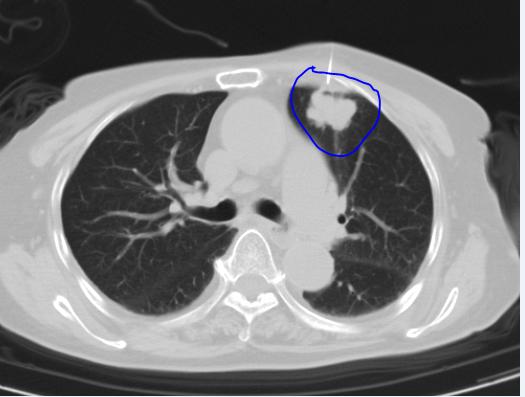

2022年1月31日,因为受凉后出现咳嗽咳痰,还有鼻塞流鼻涕,未用药,未治疗。然后就诊于当地医院,查胸部CT提示左肺上叶占位,影像具体描述是:左肺上叶团块状高密度影,大小29*23mm,呈分叶状,邻近胸膜牵拉。实际上,这样的报告,一般高度怀疑肺癌。尽管患者本人没有肿瘤家族史。

下面是该患者胸部CT胶片:

2022年2月6日入院。2022年2月11日查PETCT提示左肺上叶占位,FDG摄取增高,双肺门及纵膈较高密度淋巴结,FDG摄取增高。其中,右肺门见一超过2厘米的肿大淋巴结。胸外科认为不适合手术。